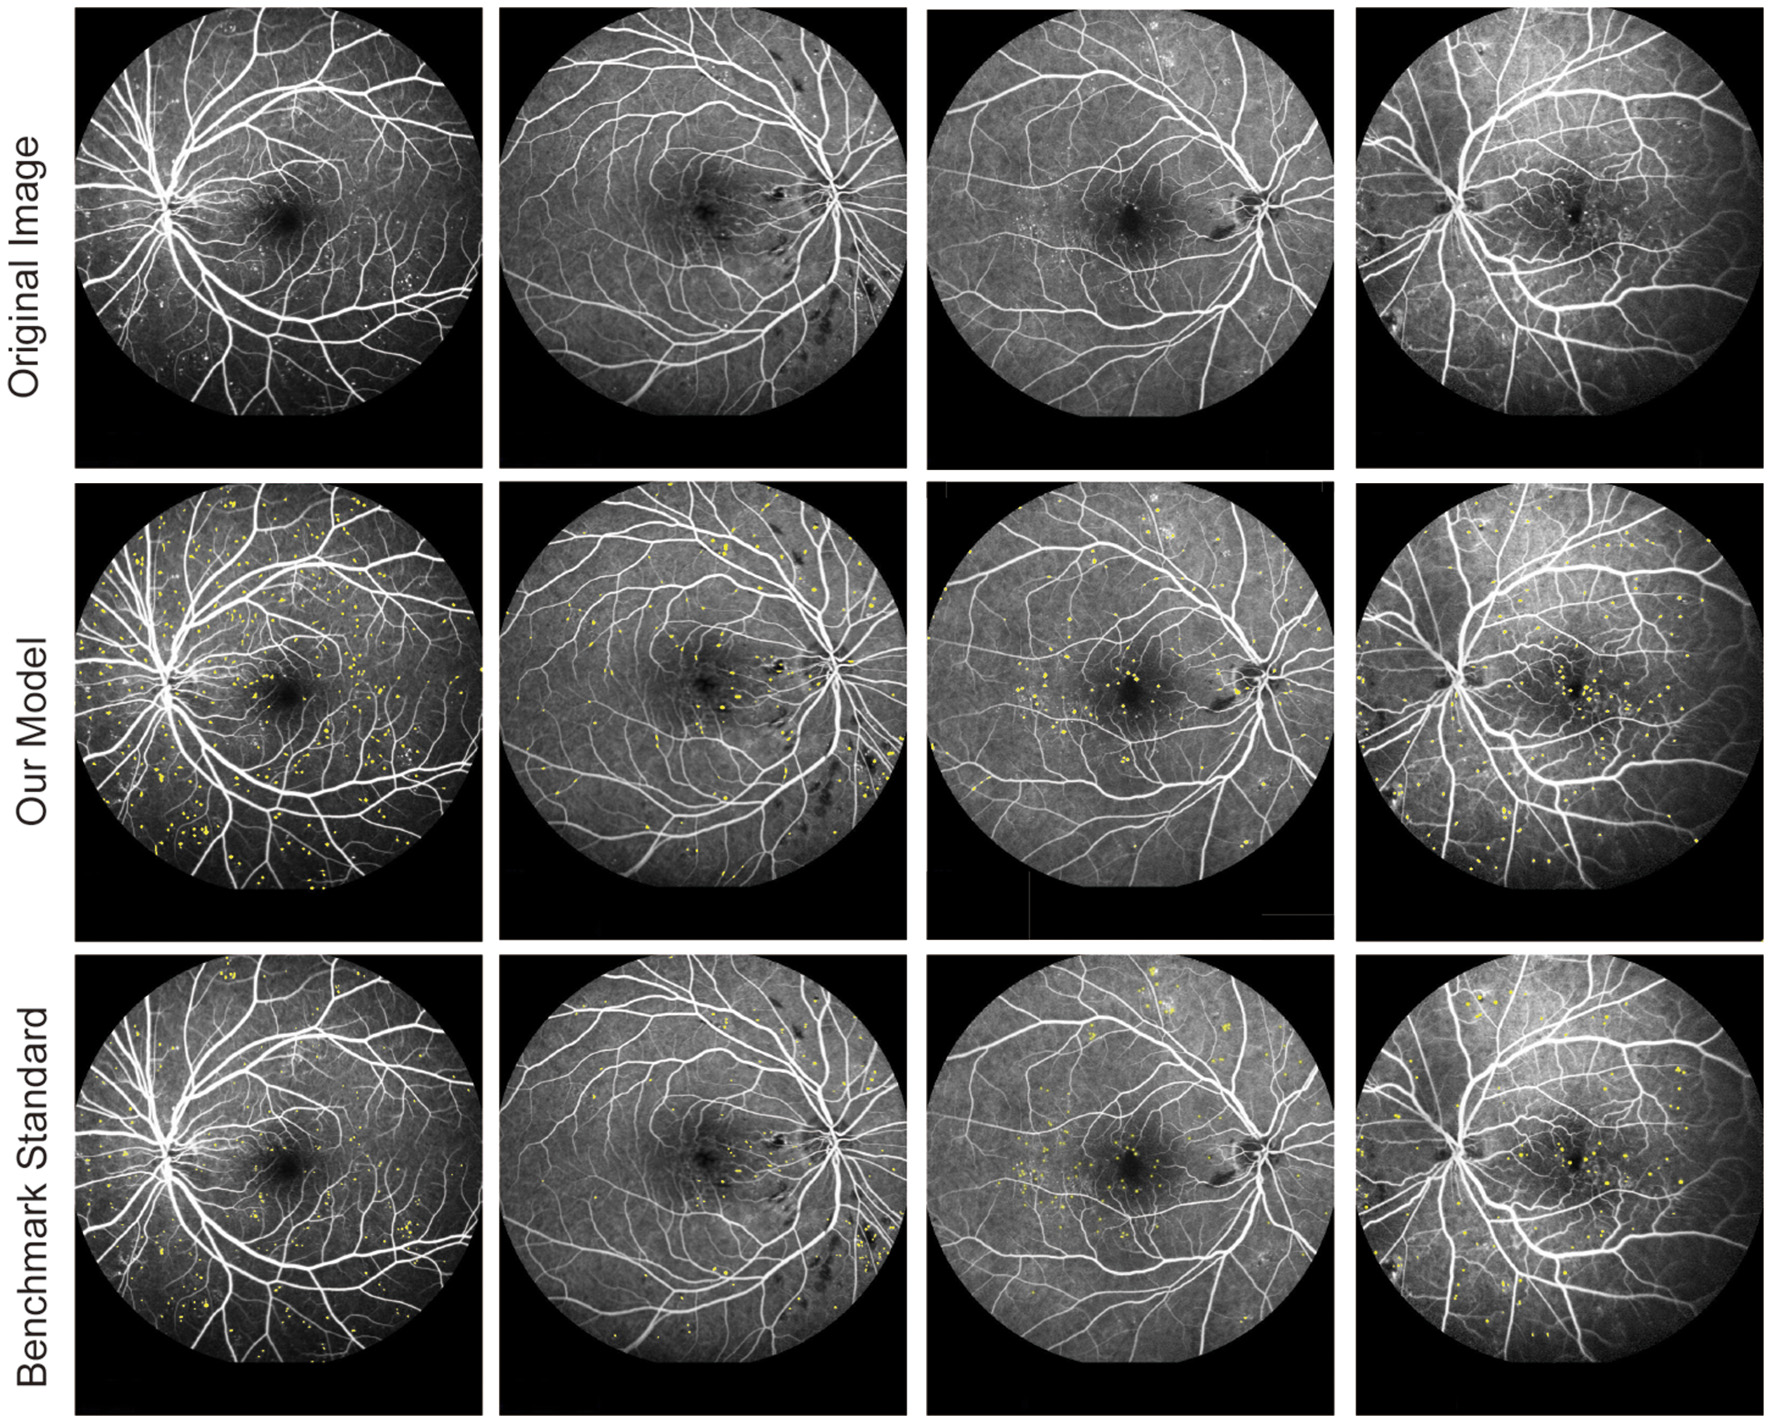

The FFA dataset comprises 1,010 FFA images, each with dimensions of 768 × 868 pixels, obtained from 65 eyes of 60 DR patients aged between 31 and 81 years. These patients underwent FFA examinations at the Eye Hospital affiliated with Nanjing Medical University between 2015 and 2019. The FFA images were captured using Heidelberg Retina Angiography (Heidelberg Engineering, Germany) by experienced clinicians. Notably, the FFA dataset did not include blurry or overexposed images. For labeling MAs in FFA images, three retinal clinicians with over 10 years of experience independently annotated MAs, serving as the benchmark standard. Patients with FFAs indicating mild or moderate DR were eligible for inclusion. The following exclusion criteria were used: (1) presence of other ocular diseases unrelated to diabetes, such as retinal arteriovenous obstruction, age-related macular degeneration, glaucoma, and uveitis; (2) any condition causing poor image quality or inability to visualize the optic disc and vessels, such as dense cataracts or corneal opacity; and (3) history of previous ophthalmological interventions, such as laser photocoagulation, vitrectomy, or anti-vascular endothelial growth factor injection. To ensure the reliability and validity of segmentation results, FFA images were independently divided into three sets: 830 images for training, 90 images for testing, and 90 images for validation. Figure 2 shows the original FFA images and MA detection results by the proposed model and benchmark standard.

Figure 2

Original fluorescein fundus angiography (FFA) images and segmentation results of MAs by the proposed model and retinal clinicians.